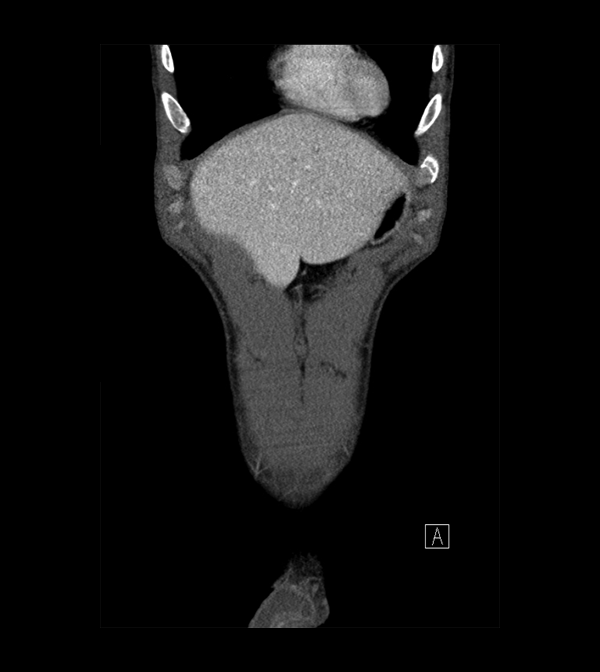

Pelvis

Covers pelvic MRI anatomy.